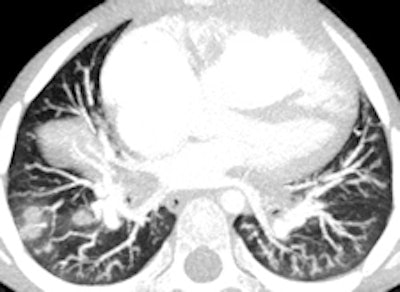

Same 14-year-old patient, there is mark dilatation of the pulmonary tree, causing compression of the trachea at the carina (top) and on the left main bronchus behind the aneurysmal right pulmonary artery (bottom)